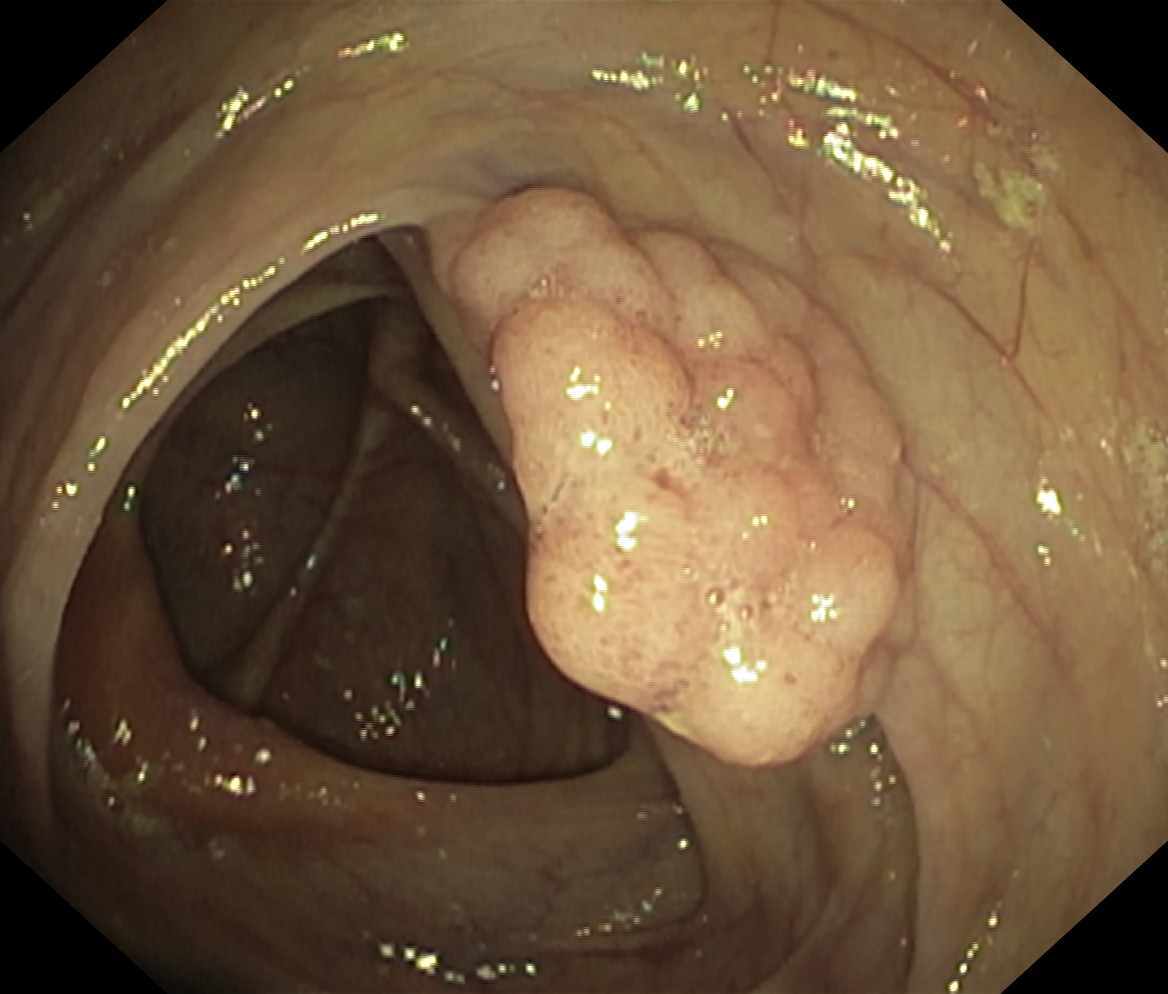

Polipy